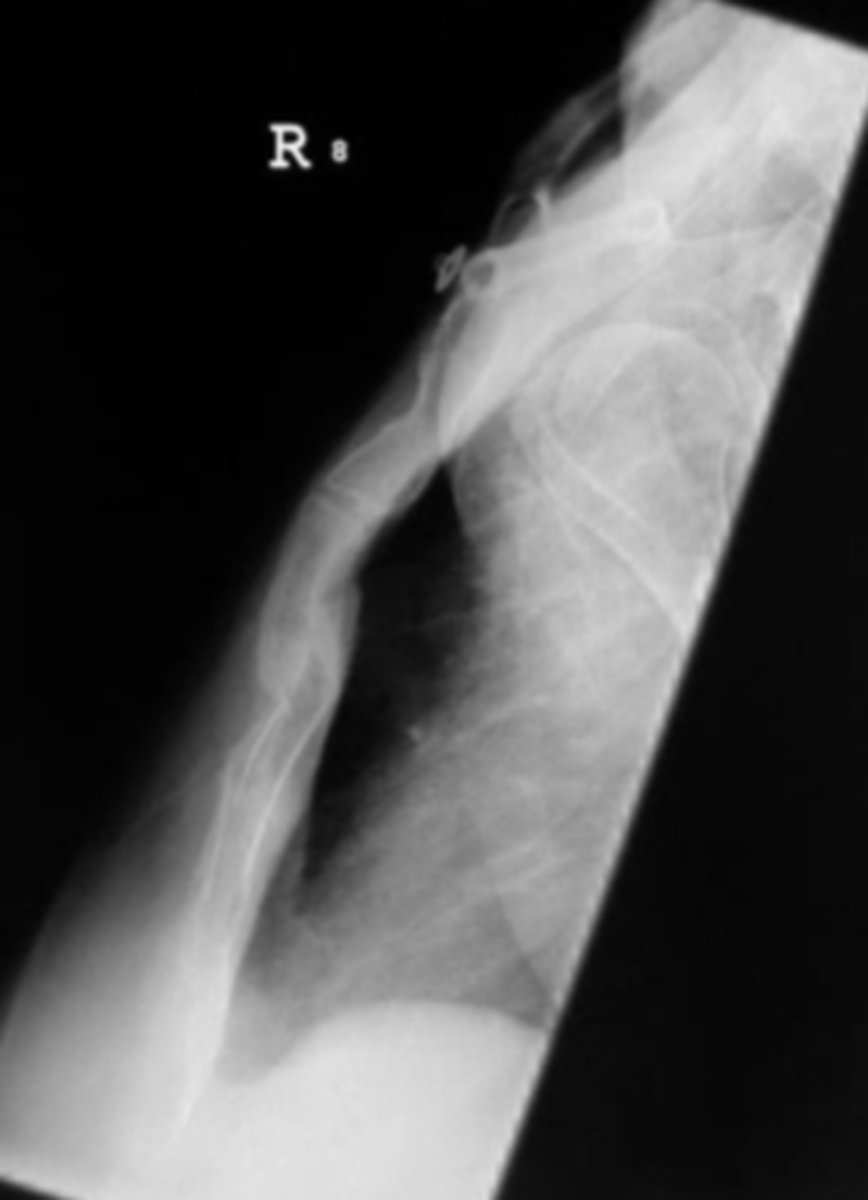

AP forearm

What view is this?